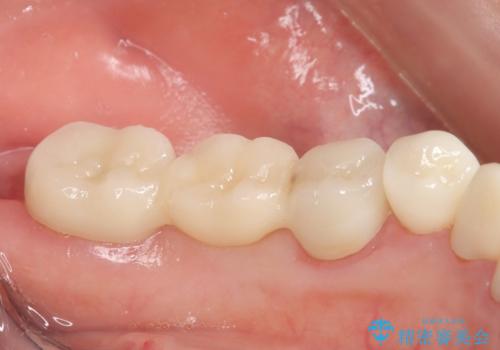

抜歯後の補綴 セラミックブリッジ治療

- 39.6万円(ジルコニアクラウン×3・仮歯×3)費用は治療当時の料金となります

前後の歯も一緒に審美性を回復することができ、喜んでいただくことができました。